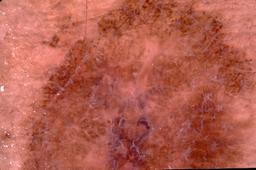

{

"age_approx": 65,

"anatom_site_general": "head/neck",

"concomitant_biopsy": true,

"dermoscopic_type": "contact non-polarized",

"diagnosis_1": "Malignant",

"diagnosis_2": "Malignant melanocytic proliferations (Melanoma)",

"diagnosis_3": "Melanoma, NOS",

"diagnosis_confirm_type": "histopathology",

"image_type": "dermoscopic",

"lesion_id": "IL_2174824",

"melanocytic": true,

"patient_id": "IP_8355925",

"sex": "male"

}